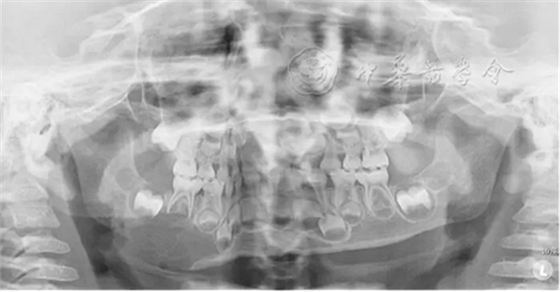

(1)疾病定義及口腔表現(xiàn):LCH是一組原因不明、以朗格漢斯細(xì)胞及其前體細(xì)胞克隆性增生為特點(diǎn)的疾病,又稱組織細(xì)胞增生癥X(histiocytosis X)。多見于20歲以下青少年。根據(jù)患者的發(fā)病年齡和臨床特點(diǎn)將其分為3型:嗜酸性肉芽腫、漢-許-克病和勒-雪病??谇活M面部常見的為骨嗜酸細(xì)胞肉芽腫,好發(fā)于下頜磨牙區(qū)與下頜角部位,病變主要為溶骨性破壞。早期表現(xiàn)為慢性炎癥和局部無(wú)痛性膨隆,病變區(qū)牙槽黏膜糜爛、潰瘍;牙齦充血,形成深牙周袋。隨著病變進(jìn)展,出現(xiàn)牙齒松動(dòng)加重,病變區(qū)鈍痛,進(jìn)食時(shí)加劇,口臭明顯。拔除松動(dòng)牙后拔牙創(chuàng)經(jīng)久不愈,觸碰牙槽窩時(shí)疼痛劇烈。影像學(xué)檢查可見骨內(nèi)圓形或橢圓形低密度影(圖2),直徑數(shù)毫米至數(shù)厘米不等,邊緣較囊腫模糊。頜骨內(nèi)病損常延伸至牙槽嵴,形成牙齒懸浮的特征性影像。牙槽骨包括牙槽中隔呈水平或垂直向吸收,牙根吸收。

圖2 4歲朗格漢斯細(xì)胞組織細(xì)胞增生癥患兒的曲面體層X線片,可見右側(cè)下頜骨大面積橢圓形低密度影